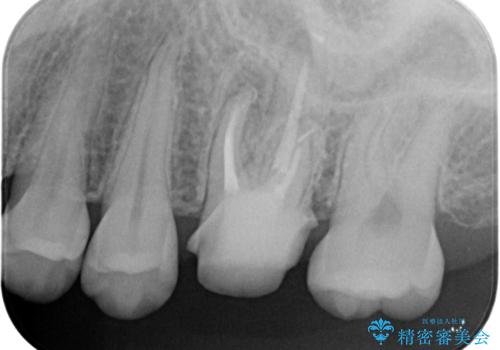

不適合な被せ物 ジルコニアクラウンでの再治療

- 検査の結果被せ物の不適合が見つかった患者様です。

ご妊娠中で安定期に治療を終わらせたいとのご希望があったため、大掛かりな外科処置は避けた治療方針で進めていきます。

被せ物を除去し、根管治療を進めた後に新しい被せ物を装着していきます。